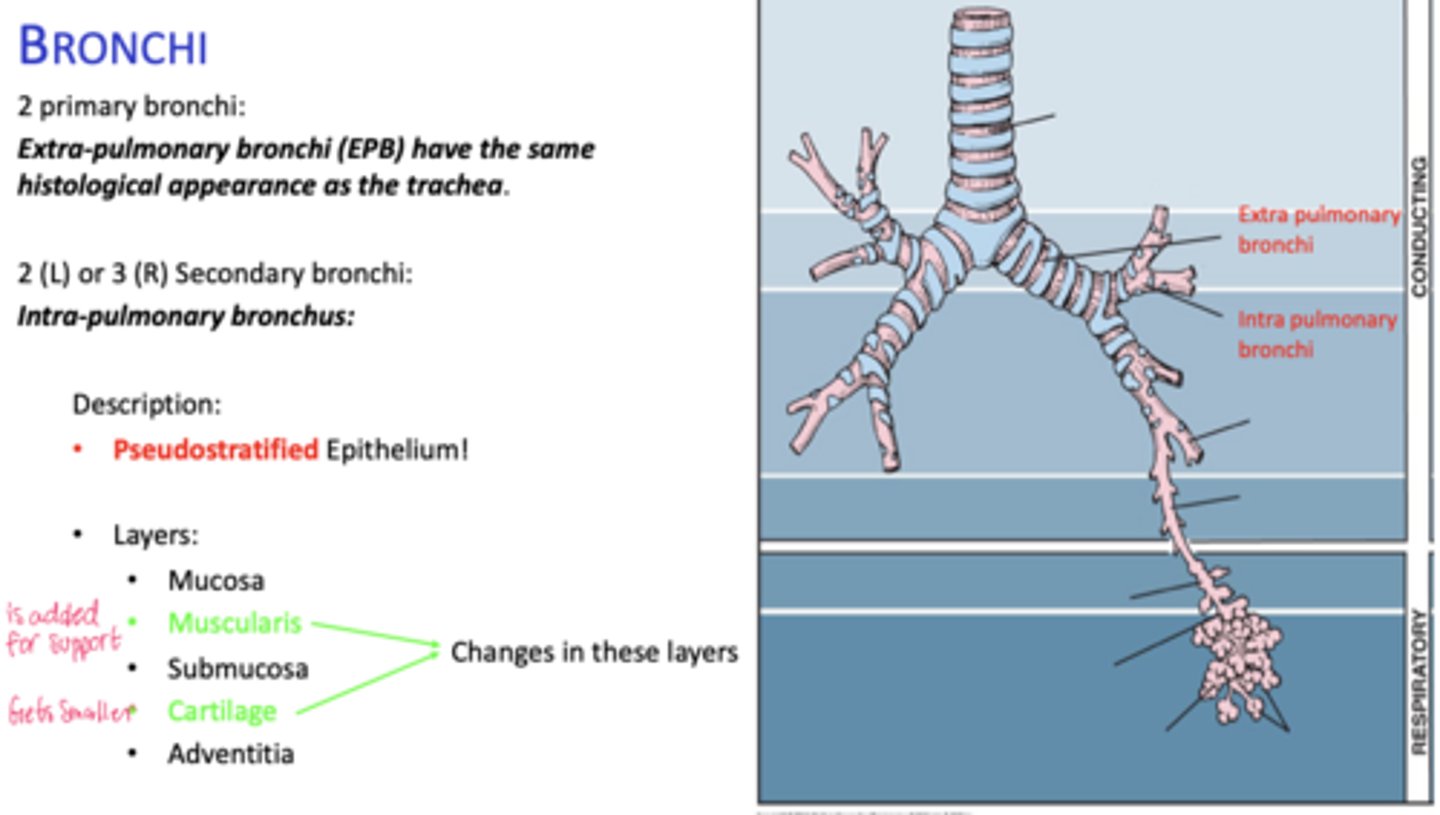

How many primary bronchi are present?

How do extrapulmonary bronchi compare histologically to the trachea?

How many secondary bronchi are in the lungs?

Two on the left, three on the right (intrapolumanry bronchus)

What happens to cartilage in intrapulmonary bronchi?

Becomes discontinuous plates.

What muscle layer is present in intrapulmonary bronchi?

Spirally oriented smooth muscle.